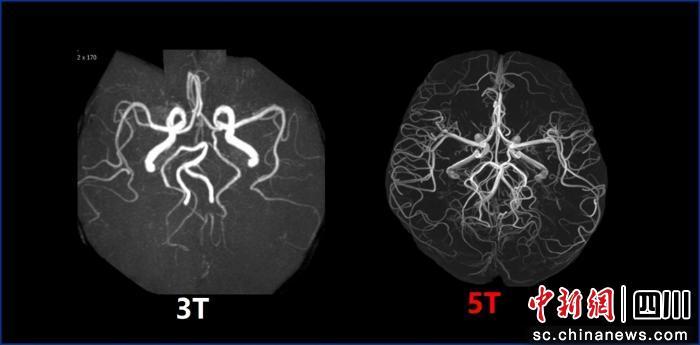

此前,臨床主流磁共振場(chǎng)強(qiáng)為1.5T和3.0T;國際上7.0T磁共振雖場(chǎng)強(qiáng)更高,但僅能實(shí)現(xiàn)頭顱及膝關(guān)節(jié)平掃,適用范圍較窄。此次投用的5.0T磁共振,相比3.0T成像清晰度大幅提升,可精準(zhǔn)識(shí)別1毫米乃至部分部位0.5毫米以下的微小病變或早期腫瘤,為疾病早診早治提供關(guān)鍵支撐;相較于7.0T,其適用場(chǎng)景更全面,可覆蓋全身成像,為中樞神經(jīng)系統(tǒng)、心血管系統(tǒng)、腹盆腔等多部位診斷提供高清影像依據(jù)。